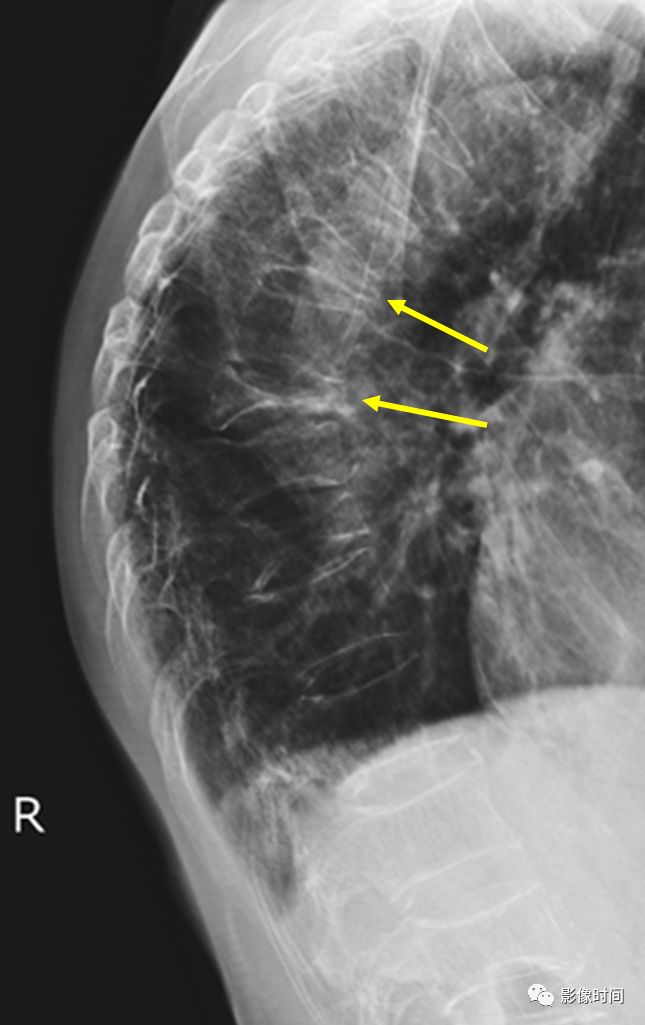

10栅栏征

栅栏征(The Palisade sign),也称灯芯绒椎体(corduroy vertebra)或灯芯绒征(corduroy sign)

脊椎椎体因病变导致骨小梁吸收、稀疏,为满足承重需要,存留的纵向骨小梁粗大;粗大骨小梁间以细条状密度减低区,形成栅栏样影像,故称栅栏征或灯芯绒椎体。

栅栏征最常见于血管瘤,以单个脊椎居多;骨质疏松如泛发性骨质增生症、老年性骨质疏松等亦可呈现此类表现,一般见于下胸椎、上部腰椎的多个椎体,只是伴有普遍的骨密度减低。有时自颈椎至腰椎全部椎体均出现栅栏征。栅栏征主要见于椎体。

典型病例

病例 1,脊柱血管瘤。胸腰椎 CT 冠状位、矢状位 MPR 重建示胸 12 椎体松质骨密度降低,其中可见粗大骨小梁呈栅栏状。

病例 2,67 岁女性,椎体血管瘤。腰椎侧位片示胸 12 及腰 3 椎体呈现栅栏征,磁共振检查证实为血管瘤。